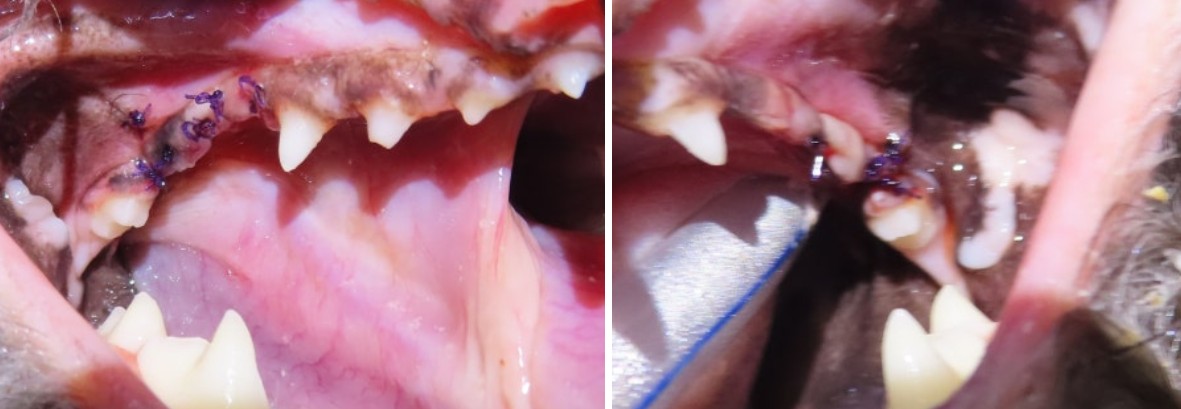

강북구 쌍문동 동물병원 비아츠에서는 양측 상악 M1을 치근 분리 후 단계적으로 제거하는 방식으로 발치를 진행했습니다.

대구치는 뿌리가 2개로 나뉘어 있고 치조골 소실이 동반된 경우 난도가 높은 치아입니다.

치근을 하나씩 분리하여 제거하고 잔존 치조골을 정리한 뒤 조직을 긴장 없이 봉합하는 방식으로 마무리했습니다.

치석 제거 후 실제 손상 범위 확인 수술 부위 세균 부하 감소 수술 예측 가능성 향상

치면을 매끄럽게 만들어 재부착을 최소화합니다.